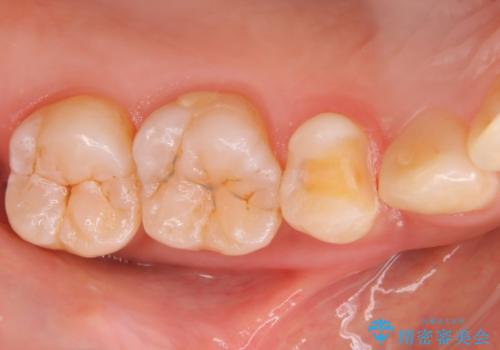

矯正終了し、銀歯が見えるため治してほしい。セラミック治療

- 当院にて矯正終了し、口腔内のモチベーションも上がったということから、銀歯をセラミックにしてほしいということで来院された患者様です。

銀歯を除去し虫歯があるか確認し、虫歯がある場合は虫歯を取ってからセラミックが入るように形を作っていきます。